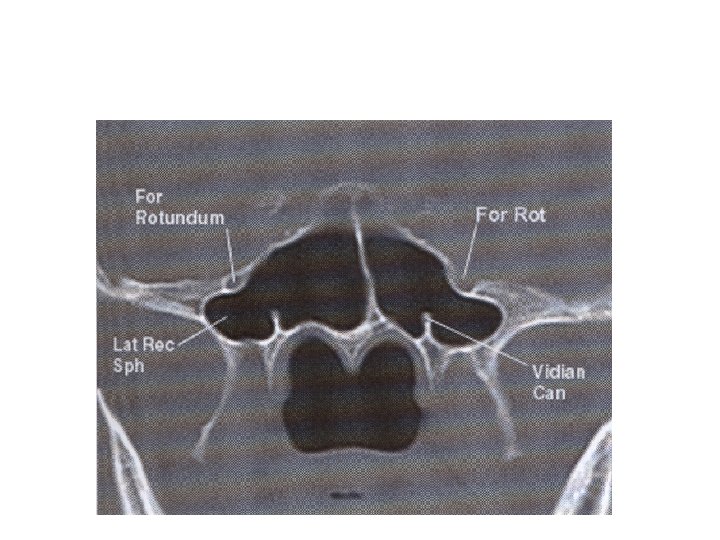

Sphenoid sinus